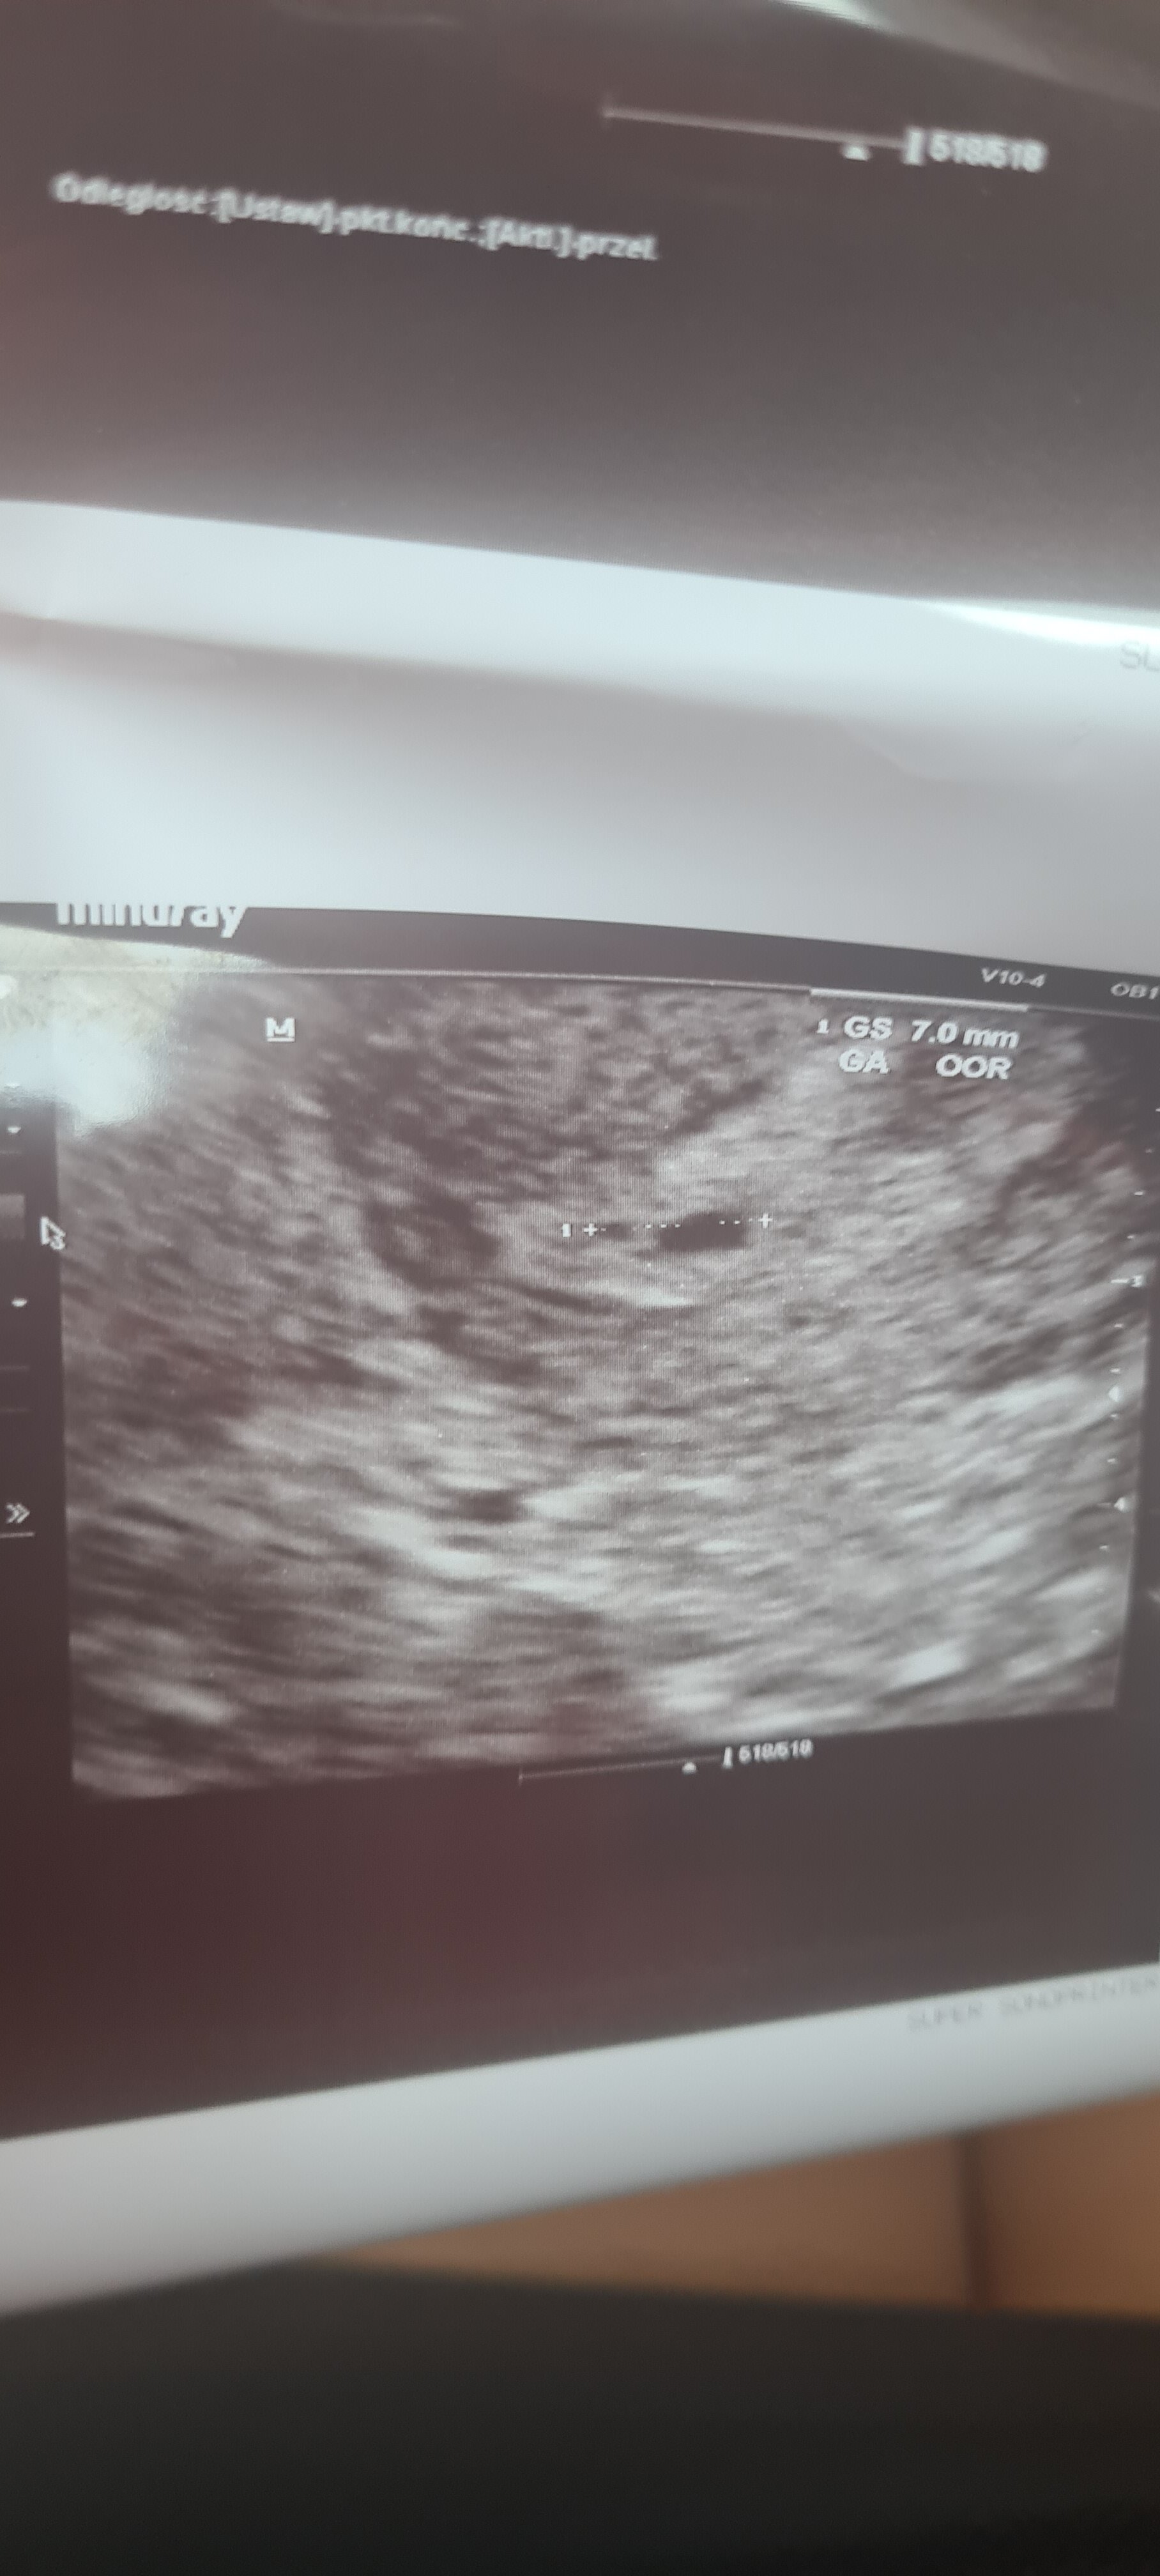

Chyba się nie udało... Puste jajo. :(

Witam, mam podobny problem. U mnie ostatnia miesiączka 04.07.21, o ciąży dowiedziałam się przed okresem. W dniu spodziewanej miesiączki miałam 2 dniowe plamienie (brązowe plamki) byłam u ginekologa w tym dniu, po beta hcg I powiększonym endometrium stwierdził że coś się dzieje ale nic nie widać. Kazał przyjść tydzień później, czyli 5tc i dalej nie potrafi określić czy to ciaza. Wrzucam usg, co myślicie?

Wg ostatniej miesiączki masz 6 tydzień, a wg USG może być mniejszy. Dużo zależy też od twoich cykli i owulacji. Może nie być jeszcze widać. Sprawdź to za tydzień u innego lekarza jeszcze.